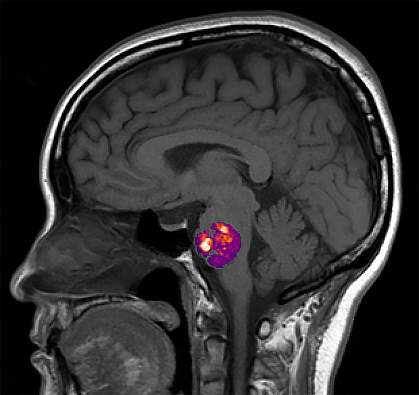

The walls of the blood vessels need to be strong and springy to handle the pressure needed to pump blood from the heart through the body. But in a condition called cavernous angioma (CA), bundles of brittle, fragile blood vessels form in the brain, spinal cord, or both.

Blood can stagnate in these fragile bundles, also called cerebral cavernous malformations, and leak into the brain. This can lead to headaches, seizures, or brain hemorrhages. Medications can lessen these symptoms, but the primary treatment for CA is surgical removal.